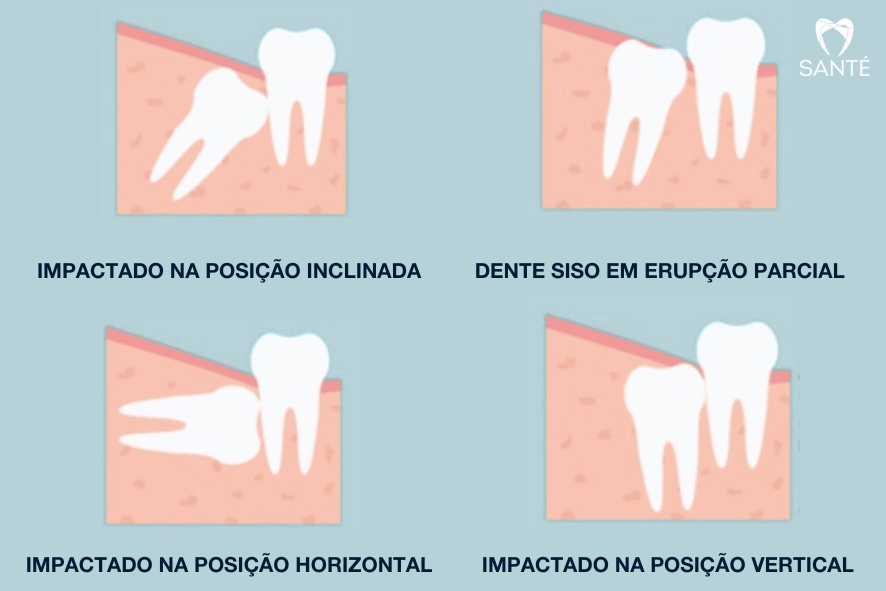

O dente siso (terceiro molar ou dente ciso) costuma nascer entre os 16 e 25 anos. Mas não se engane, mesmo quando o siso não nasce ou não causa dor ele pode precisar de extração, sua retirada é indicada quando ele causa:

Um siso mal posicionado pode causar problemas no dente vizinho como: cárie, perda óssea, tratamento de canal e até extração, com necessidade de reposição por meio de implante dentário.

O valor da extração do siso em BH varia conforme a complexidade (nascido, semi-incluso, incluso), a necessidade de exames de tomografia e a necessidade de sedação. Na Santé, priorizamos que a cirurgia seja realizada por um cirurgião bucomaxilofacial, o que garante menos riscos, procedimentos mais rápidos e um pós-operatório mais tranquilo. O orçamento final é definido após avaliação clínica e radiográfica do siso (ou ciso).

A indicação depende de espaço, posição e riscos ao dente vizinho do siso. Em geral, a remoção do ciso é mais simples na juventude, a partir dos 16 anos, antes das raízes estarem totalmente formadas. Avaliação individual define o melhor momento para tirar o siso.

Não. Se o siso/ciso estiver bem posicionado, possibilita a higiene adequada e sem causar danos, pode ser apenas acompanhado. Indica-se remoção do siso quando há dor, cárie, pericoronarite ao redor do siso, cistos ou risco ao dente vizinho.

Em média, cada siso leva 20 a 60 minutos para ser extraído, variando com a inclusão e anatomia. Cirurgias de siso/ciso incluso tendem a ser mais longas, mas o planejamento correto torna o procedimento previsível e seguro.

Sim, pode doer: o siso semi-incluso (siso deitado) favorece acúmulo de placa e pericoronarite (inflamação da gengiva do siso). O tratamento inclui higienização do local pelo dentista, medicação para inflamação do siso e, quando indicado, extração programada.